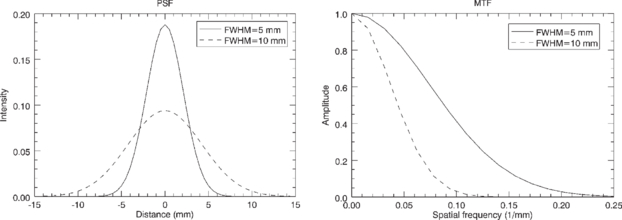

The Fourier transform of the PSF is known as the modulation transfer function (MTF). The MTF contains the same information as the PSF, but expressed in the frequency domain rather than in the spatial domain. The Fourier transform of a Gaussian function is also a Gaussian function, and the widths of the two functions have an inverse correlation: as the spatial domain Gaussian becomes broader, the frequency domain Gaussian becomes narrower, and vice-versa (see figure 2). The operation of convolution with a PSF in the spatial domain is equivalent to multiplication with the corresponding MTF in the frequency domain. This means that a PET or SPECT image can be described in the frequency domain as the product of the Fourier transform of the true activity distribution and the MTF of the system. Image components corresponding to mid-range frequencies, although attenuated, may still be present in the data and could in principle be restored by an inverse filtering operation. On the other hand, image components at higher frequencies, where the MTF is essentially zero, will be lost forever from the data. Attempts to restore these image components usually lead to noise-amplification or image artefacts.

Figure 2. Point spread functions with FWHM of 5 and 10 mm (left), and corresponding modulation transfer functions (right).